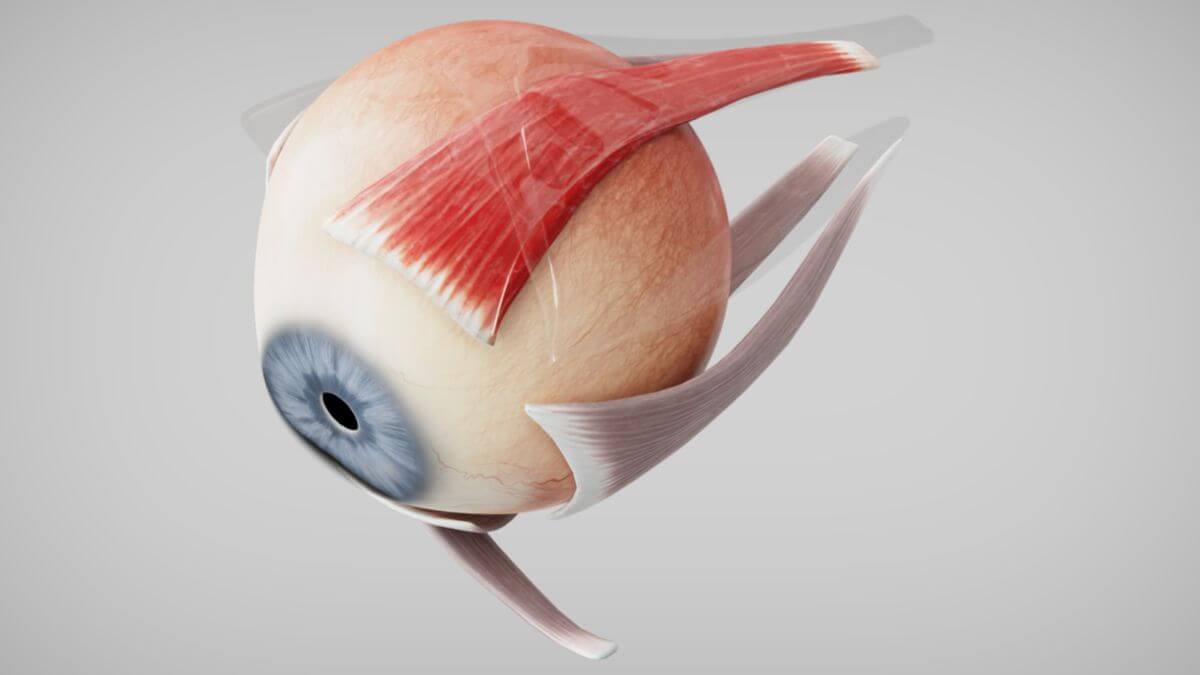

Die Muskeln

Im Bereich um das Auge herum gibt es eine Vielzahl von Muskeln. Das sind zum einen die Muskeln, die für die Bewegung des Auges selbst verantwortlich sind. Auf der anderen Seite gibt es mehrere Muskeln, die für die Mimik verantwortlich sind.

Der Muskulus levator palpebrae superioris gehört zu den äußeren Augenmuskeln und verläuft oberhalb des Musculus rectus superior (https://flexikon.doccheck.com/de/Musculus_levator_palpebrae_superioris). Das Anspannen des Musculus rectus superior sorgt dafür, dass das Auge nach oben gedreht wird (https://flexikon.doccheck.com/de/Musculus_rectus_superior). Der Muskulus levator palpebrae superioris ist veräntwortlich für das heben des obenren Augenlids und somit das Öffnen des Auges. Er wird außerdem agonistisch, also gleichzeitig, mit dem MRS angespannt und sorgt dafür, dass das Augenlid beim Nach-Oben-Schauen angehoben wird und somit die Pupillen nicht verdeckt (TODO: das nicht verdecken ist bisher frei erfunden, QUELLE).

Muskulus levator palpebrae superioris:

Musculus rectus superior:

Musculus rectus superior: